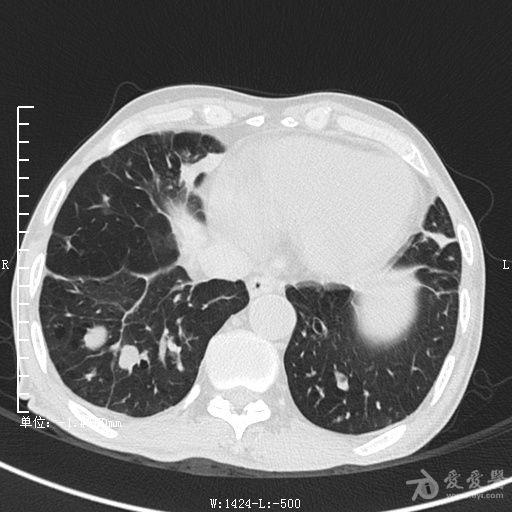

典型支气管扩张及肺水肿CT片

典型支气管扩张肺水肿